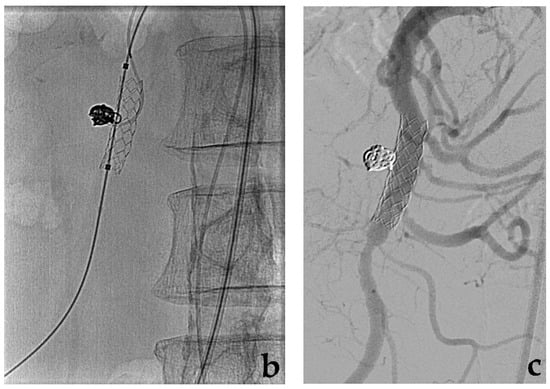

4. Covered Stent

- Venturini, M.; Marra, P.; Colombo, M.; Panzeri, M.; Gusmini, S.; Sallemi, C.; Salvioni, M.; Lanza, C.; Agostini, G.; Balzano, G.; et al. Endovascular repair of 40 visceral artery aneurysms and pseudoaneurysms with the Viabahn Stent-Graft: Technical aspects, clinical outcome and mid-term patency. Cardiovasc. Interv. Radiol. 2018, 41, 385–397. [Google Scholar] [CrossRef]

- Venturini, M.; Angeli, E.; Salvioni, M.; De Cobelli, F.; Trentin, C.; Carlucci, M.; Staudacher, C.; Del Maschio, A. Hemorrhage from a right hepatic artery pseudoaneurysm: Endovascular treatment with a coronary stent-graft. J. Endovasc. Ther. 2002, 9, 221–224. [Google Scholar] [CrossRef] [PubMed]